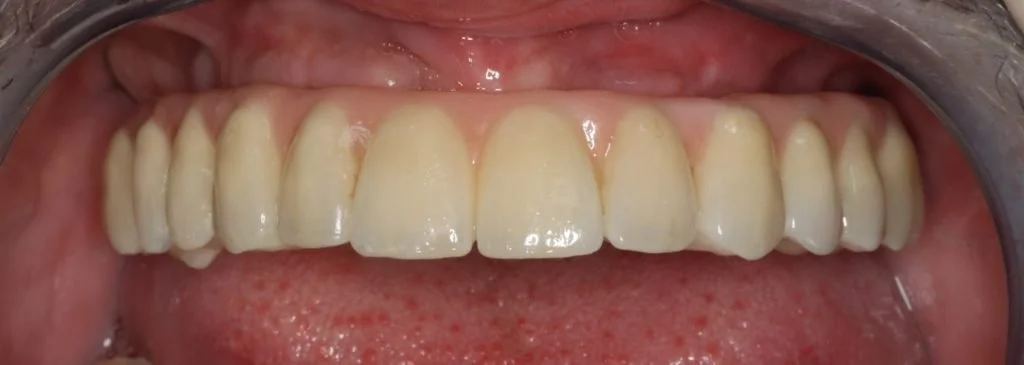

Records stage: due to the fact that all records were gained by the adjustment and confirmation of the provisional removable complete maxillary denture, records were quite straightforward. The complete denture was copied, flanges were removed, and the resulting guide was then seated over the existing tissue level healing abutments. A PMMA bridge with plastic inserts was constructed digitally in the laboratory and sent for final confirmation prior to construction of the definitive porcelain-fused-to-zirconia bridge. The definitive bridge was inserted and radiographs were taken to confirm full seating and correct emergence profile. Once passivity of fit was confirmed, abutments crews were torque to 35 Ncm, and the access cavities were restored with PTFe tape and composite resin. The occlusion was adjusted to ensure guiding services were smooth, concave and gradually increasing pre-truce in steepness, and smooth shared group function in lateral excursion.

Photo and X-ray at 2 year review